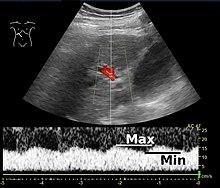

Imaging

Doppler ultrasonography of the portal vein over 5 seconds, showing peaks of maximal velocity, as well as points of minimal velocity.

Ultrasound is routinely used in the evaluation of cirrhosis. It may show a small and nodular liver in advanced cirrhosis along with increased echogenicity with irregular appearing areas. Other liver findings suggestive of cirrhosis in imaging are an enlarged caudate lobe, widening of the fissures and enlargement of the spleen. An enlarged spleen (splenomegaly), which normally measures less than 11–12 cm in adults, can be seen and may suggest underlying portal hypertension. Ultrasound may also screen for hepatocellular carcinoma, portal hypertension, and Budd-Chiari syndrome (by assessing flow in the hepatic vein). An increased portal vein pulsatility is an indicator of cirrhosis, but may also be caused by an increased right atrial pressure.[37] Portal vein pulsatility can be quantified by pulsatility indices (PI), where an index above a certain cutoff indicates pathology:

Pulsatility indices (PI)

Index Calculation Cutoff

Average-based (Max – Min) / Average[37] 0.5[37]

Max-relative (Max – Min) / Max[38] 0.5[38][39]–0.54[39]